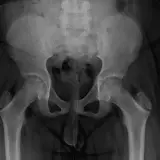

Over 2,100 interactive radiology cases, curated by radiologists for your level of training. Scroll, window, and view cases full screen — just like on PACS. Click linked findings in each writeup to jump straight to them on the image. Cases include sample reports, a focused discussion section, original illustrations, and videos.

完全交互式病例,配备您在 PACS 上期待的各项工具——滚动、调窗、缩放、平移、测量、ROI 和全屏模式。

丰富的标注直接在病例图像上突出关键发现。点击病例讲解中的关联发现,即可跳转至其在扫描上的精确位置。